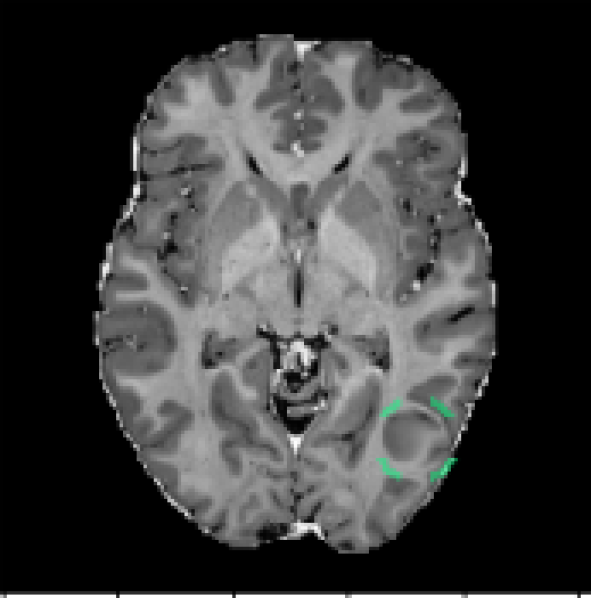

Figure 9 displays anomalous examples from the DeepLesion dataset with bounding box labels for each lesion. The outputs from each method show varying levels of sensitivity. MMD-VAE exhibits reconstruction errors throughout the images which reflects the difficulty of learning a compact representation for data with high variation and detail. VQ-VAE2 uses a hierarchical architecture to produce higher fidelity reconstructions with less error. However, this does not help the network to be sensitive to specific irregularities such as lesions. Using the VQ-VAE2 for image restoration can help to highlight regions based on likelihood, rather than purely on intensity differences. This approach can be more selective, but it also tends to highlight certain natural variations that may be deemed less likely. Meanwhile, StyleGAN searches for a normal matching image in its latent space, but it is not always possible to find a good match when the data has complex and detailed structures that can vary greatly across images. In comparison to the reconstruction-based methods, FPI highlights more specific areas in the image that contain lesions or other unusual elements that are not lesions. Finally, the supervised method gives the most lesion-specific activations which can only be learned through labelled examples.